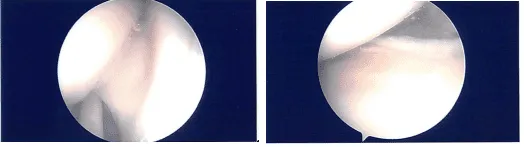

Se realizó un portal de entrada lateral y se introdujo el telescopio. Había ____ en la rótula así como en el cóndilo femoral medial, que tras hacer un portal medial, se limpiaba artroscópicamente con una afeitadora.

El examen del menisco medial mostró una rotura del cuerno anterior del menisco medial, que estaba limpia. La muesca intercondilar mostraba un LCA intacto. El examen del compartimento tibiofemoral lateral fue normal.

Tras un riego exhaustivo, se guardaron las fotos finales y se cerró la herida. Luego, se inyectaron 40 mg de Depo-Medrol en la rodilla izquierda tras la cirugía.